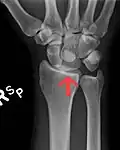

Left hand anterior view (palmar view). Lunate bone shown in red.

The lunate bone (semilunar bone) is a carpal bone in the human hand. It is distinguished by its deep concavity and crescentic outline. It is situated in the center of the proximal row carpal bones, which lie between the ulna and radius and the hand. The lunate carpal bone is situated between the lateral scaphoid bone and medial triquetral bone.

The lunate is a crescent-shaped carpal bone found within the hand. The lunate is found within the proximal row of carpal bones. Proximally, it abuts the radius. Laterally, it articulates with the scaphoid bone, medially with the triquetral bone, and distally with the capitate bone. The lunate also articulates on its distal and medial surface with the hamate bone.[2]: 708 [3]

The proximal surface of the lunate bone is smooth and convex, articulating with the radius. The lateral surface is flat and narrow, with a crescentic facet for articulation with the scaphoid bone. The medial surface possesses a smooth and quadrilateral facet for articulation with the triquetral bone. The palmar surface is rough, as is the dorsal surface. The dorsal surface is broad and rounded. The distal surface of the bone is deep and concave.[4]